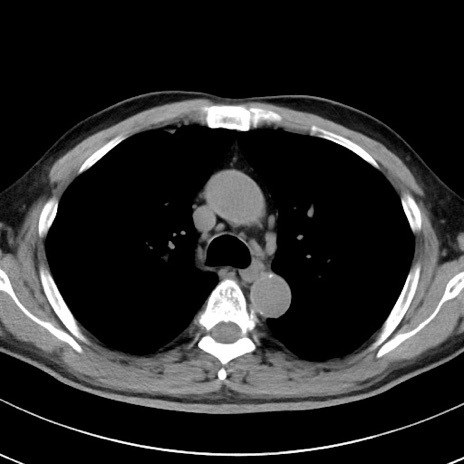

【腹部TIPS】症例29 参考症例 CT(横断像)

症例

70歳代男性